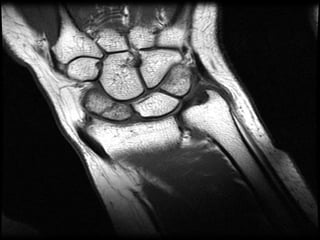

MRI

• T1-weighted images obtained in a single plane (coronal) are

typically sufficient to determine the presence of a scaphoid

fracture.

• Gaebler prospectively performed MRI on 32 patients, at

average of 2.8 days post injury

– 100% sensitivity and specificity

• In recent study Dorsay has shown that immediate MRI

provides cost benefit when compared to splintage and repeat

xray

• False positives due MRI’s sensitivity to marrow oedema

MRI • T1-weighted imagesobtained in a single plane (coronal) are typically sufficient to determine the presence of a scaphoid fracture. • Gaebler prospectively performed MRI on 32 patients, at average of 2.8 days post injury – 100% sensitivity and specificity • In recent study Dorsay has shown that immediate MRI provides cost benefit when compared to splintage and repeat xray • False positives due MRI’s sensitivity to marrow oedema